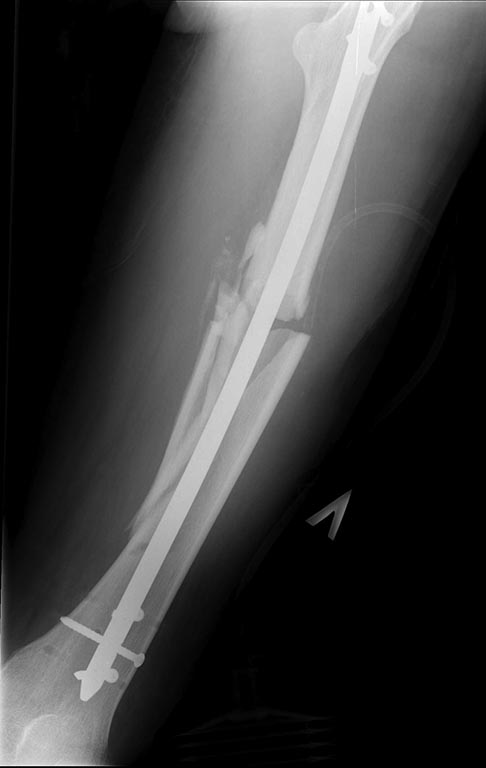

Добрый день уважаемые коллеги. Вашему вниманию представляю

пациента(мужчина, 30 лет).

Тяжелая сочетанная травма 7 мес. назад. Из скелетной травмы: открытый

перелом бедра, открытый перелом дистального метаэпифиза левого плеча,

закрытый перелом шейки левого плеча). Все повреждения были

прооперированы.Бедро синтезировано штифтом Остеомед d-11мм.

прилагаю). основной вопрос, тактический, чем лучше выполнить

реостеостеосинтез. У нас в наличии имеется: из штифтов Остеомед d-12мм,

старый набор Синтез с канюлированными штифтами максимальный d-14мм.,

пластины LC-DCP, аппарат Илизарова.

В плане 2 варианта: 1) удаление проксимальных блокирующих

винтов(сломаный тоже), фиксация бедра спице-стержневым аппаратом из 2-х

опор и компрессия в аппарате.

2)удаление металлоконструкции, и выполнение реостеосинтеза с

рассверливанием( учитывая очень широкий канал) с установкой винтов

поллеров в дистальном отломке. Жду ваших предложений и мнений. Спасибо